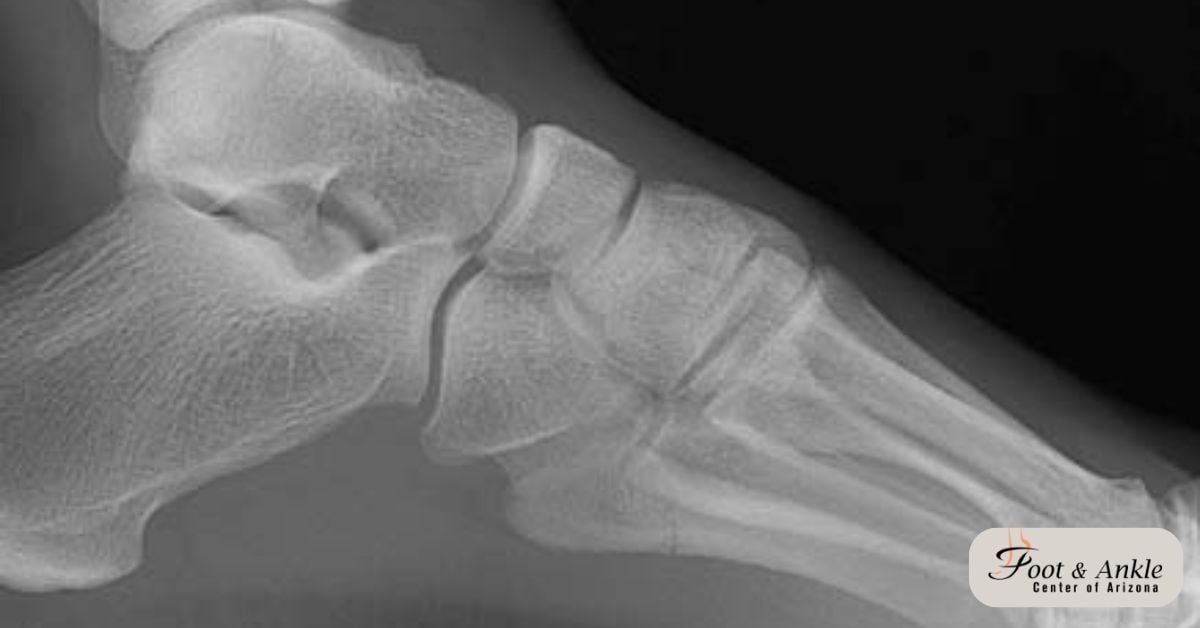

Understanding the 5th Metatarsal Fracture

The fifth metatarsal is one of the 5 lengthy bones within the foot, and its base is placed on the outer aspect of the foot. Fractures right here can be painful and debilitating, frequently attributable to acute injuries including twisting the foot or direct effects. Without proper remedy, those fractures can result in chronic pain, instability, and arthritis.

- How is a base of 5th metatarsal fracture diagnosed?

Diagnosis is made through bodily exam and imaging assessments which includes X-rays or MRI scans to decide the extent of the fracture.